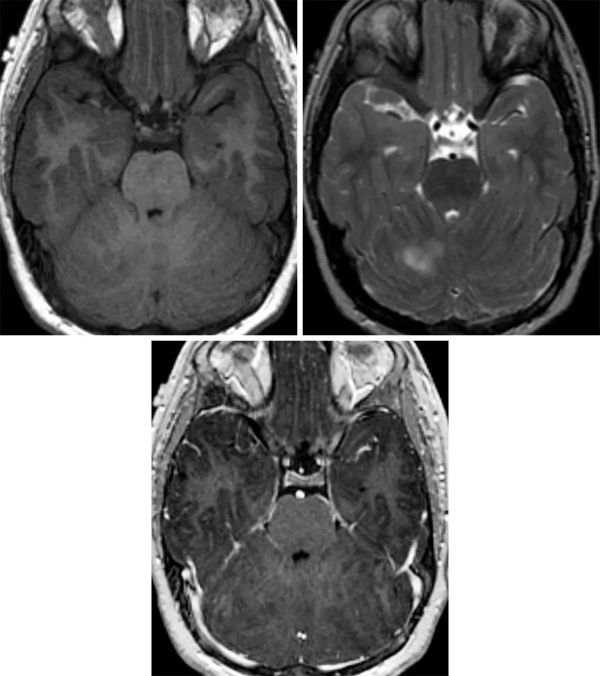

小脑发育不良性节细胞瘤的MRI特征是小脑小叶扩大伴结构扭曲,以及不同程度的囊性变。增强MRI扫描病灶通常无强化,T1像呈低信号,T2像以高信号与低信号交替的层状模式为特征。肿块为局限性,与周围组织界限分明。在少数病例中,对比增强扫描出现强化,这可能代表小脑皮质的外层有静脉增生和的引流静脉。